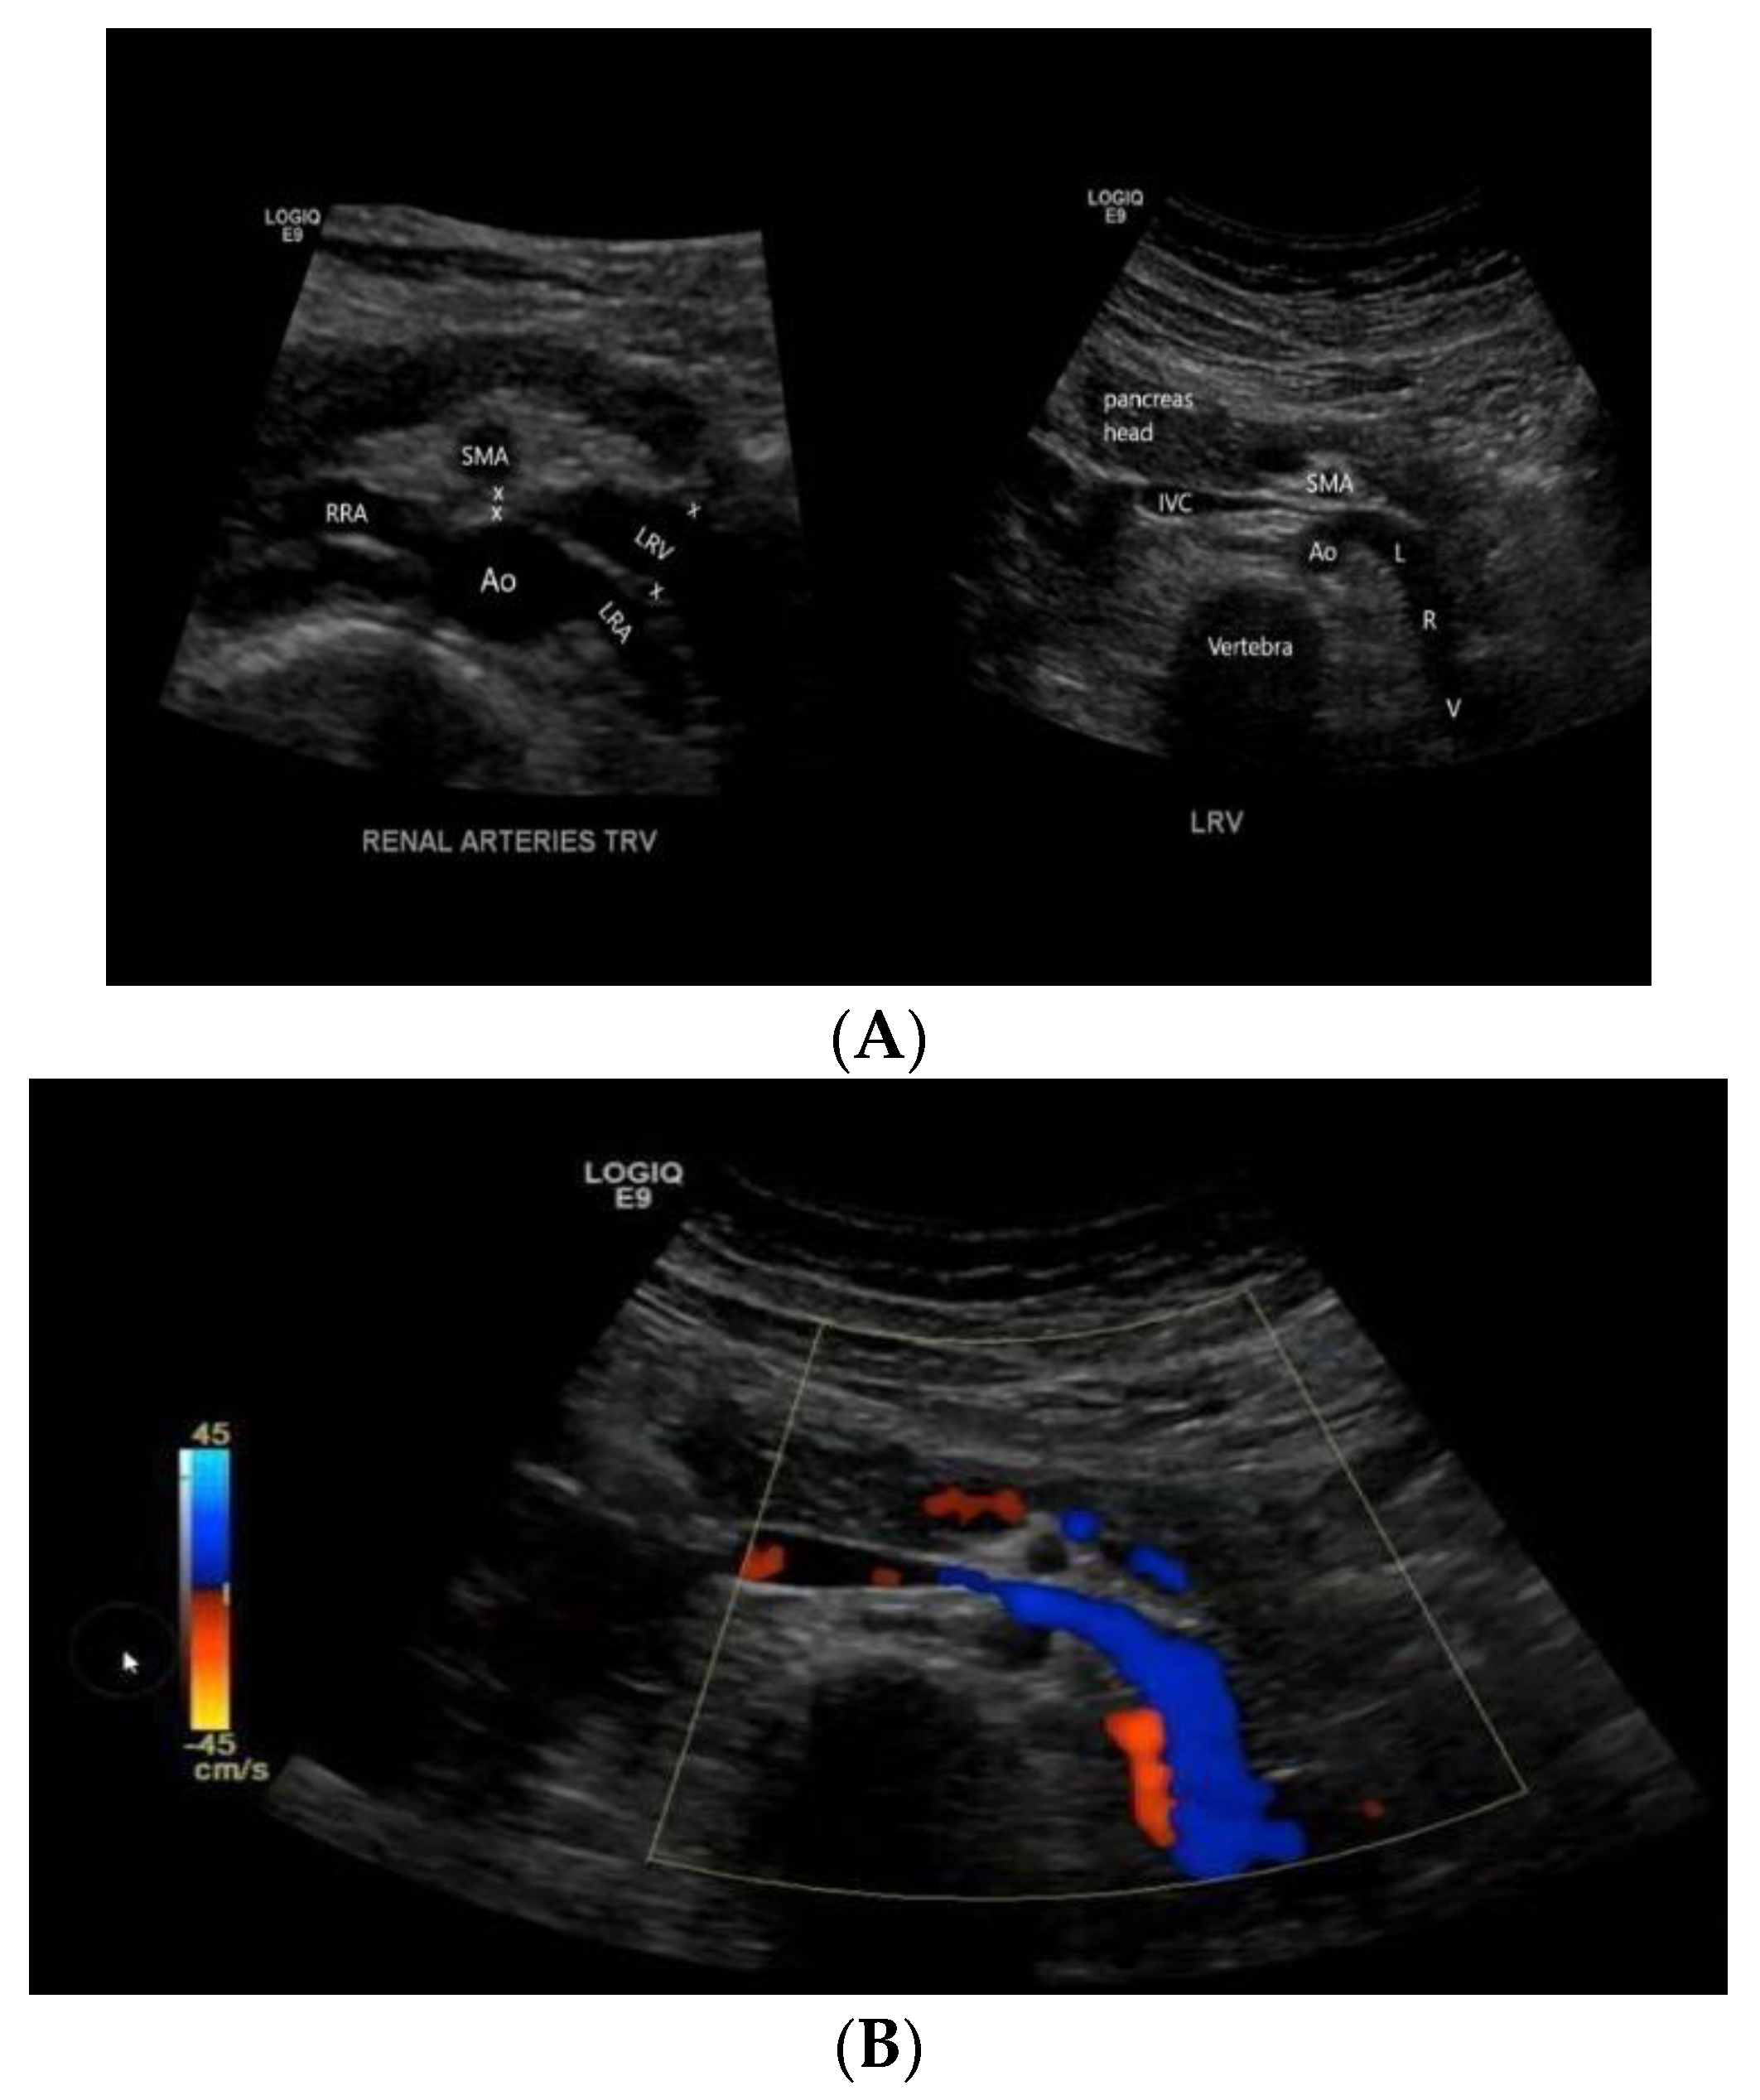

2.1. Case 1

2.2. Case 2